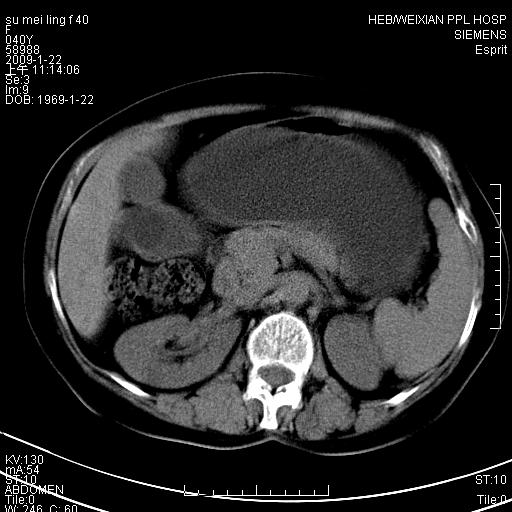

主因食欲不振检查。b超检查肝内片状低密度影。

图象的序列乱,病史也简单,单看这几幅图片考虑——肝囊肿?转移瘤?建议强化

以肝多发性囊肿可能大

我个人认为转移瘤可能性大!建议增强!

考虑多发肝小囊肿,建议增强,不排除囊性转移可能。

多发肝囊肿或caroli

肝内多发囊性低密度灶,以肝囊肿可能性大;建议必要时行进一步检查。

囊性病变沿胆管走向,首先考虑肝内胆管囊肿(caroli)、多发肝囊肿不除外